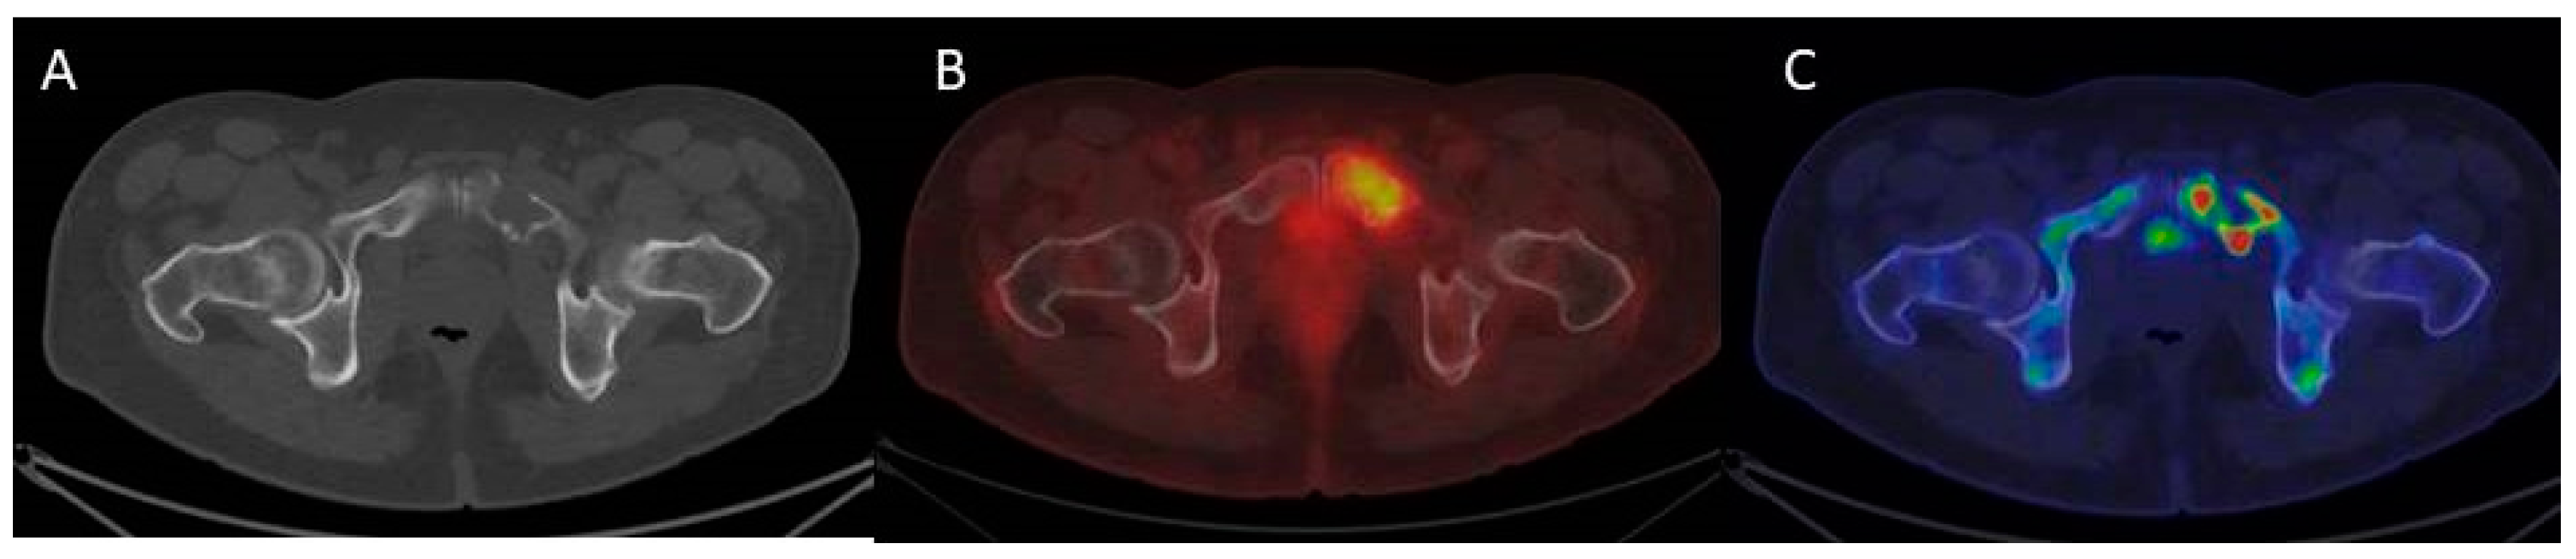

3.4. The Evolving Role of FDG-PET/CT in Multiple Myeloma